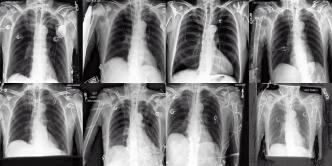

Chest X-rays We use the CheXpert dataset 10.1609/aaai.v33i01.3301590 , which contains 170k training images. This dataset contains diversity in medical devices (such as chest tubes and wires), diseases (such as pneumonia and pleural-effusion) and anatomical details. We implement Rainbow on top of frozen parameters of a finetuned Stable Diffusion v1.5 (SD1.5) by previous work kumar2025prism for chest X-ray data. We generate 2D chest X-ray images based on text prompt conditions, e.g., "Chest X-ray showing Support Devices". In addition to the finetuned SD1.5, we include RadEdit perez2024radedit , a model trained from scratch on multiple chest radiology data such as CheXpert irvin2019chexpert , MIMIC-CXR johnson2019mimic , and NIH-CXR wang2017chestxray data for image editing tasks (more details at Appendix D.3), in the result comparison. Rainbow’s graph generator module includes , , and .

Chest X-rays Figure 4b quantifies generations by Rainbow and baselines using FID and VS. Rainbow achieves a higher VS, indicating greater diversity than the finetuned SD model, while also improving image quality with a lower FID score. Both Rainbow and SD outperform the RadEdit. Figure 6 provides a qualitative comparison, images are generated using the prompt "Chest X-ray showing support devices", where Rainbow generates a more diverse set of medical devices, such as pacemakers, in all generations, while baselines do not show any devices in some images. All models achieve similar CLIP scores of . Additional results including generations, Figure 22 and numeric results, Table 4, are outlined in Appendix E.

We apply the same approach to chest X-rays to explore the set of "support devices" edges by extracting the 10 most frequently added edges when changing the prompt from "Chest X-ray with no significant finding" to "Chest X-ray showing support devices" (visualized in Figure 25 in Appendix E). Figure 8 shows the transformation with added "support devices" edges into trajectories with the appearance of medical devices in the generated images.